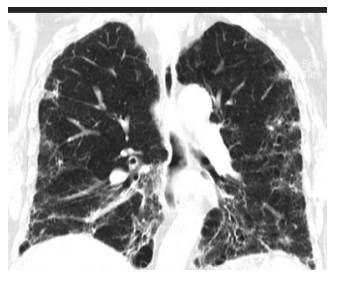

A 70-year-old man previously healthy presented with symptoms including low-grade fever, dry cough, and breathlessness. His oxygen saturation dropped to 88% on room air, and imaging revealed extensive ground-glass opacities in the lungs. Despite treatment with oxygen therapy, corticosteroids, and antiviral medications, his condition worsened before gradually improving. After 28 days, he was diagnosed with post-COVID lung fibrosis, marked by reticulations, bronchiectasis, and architectural distortion visible on HRCT imaging. He was discharged with continued oxygen therapy, antifibrotic medication, and pulmonary rehabilitation but was lost to follow-up.

Fig 1: A 70-year-old man's chest CT thorax images reveal diffuse ground glass opacities in both lungs, with some apico-basal gradient and tiny cysts or hyperlucent spaces. The CT thorax image shows extensive reticulations, architectural distortion, ectasis of bronchi and bronchioles, and hyperlucency of intervening areas.